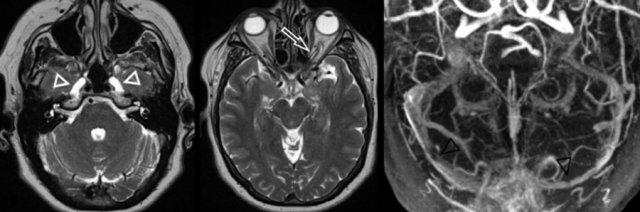

Bên trái là hình ảnh đường đi bất thường của động mạch cảnh trong (mũi tên) và sự tồn tại dai dẳng của động mạch bàn đạp (đầu mũi tên) trên CT lát mỏng.

Lưu ý sự vắng mặt của lỗ gai (encircled).

Hình ảnh CISS T2W nặng bên trái cho thấy xung đột thần kinh-mạch máu của động mạch tiểu não sau dưới với sự chèn ép và di lệch dây thần kinh mặt và dây thần kinh tiền đình-ốc tai (hình bên trái, đầu mũi tên đen).

Hình bên phải cho thấy vòng mạch độ 3 (>50%) của động mạch tiểu não trước dưới trong ống tai trong bên trái (mũi tên trắng).